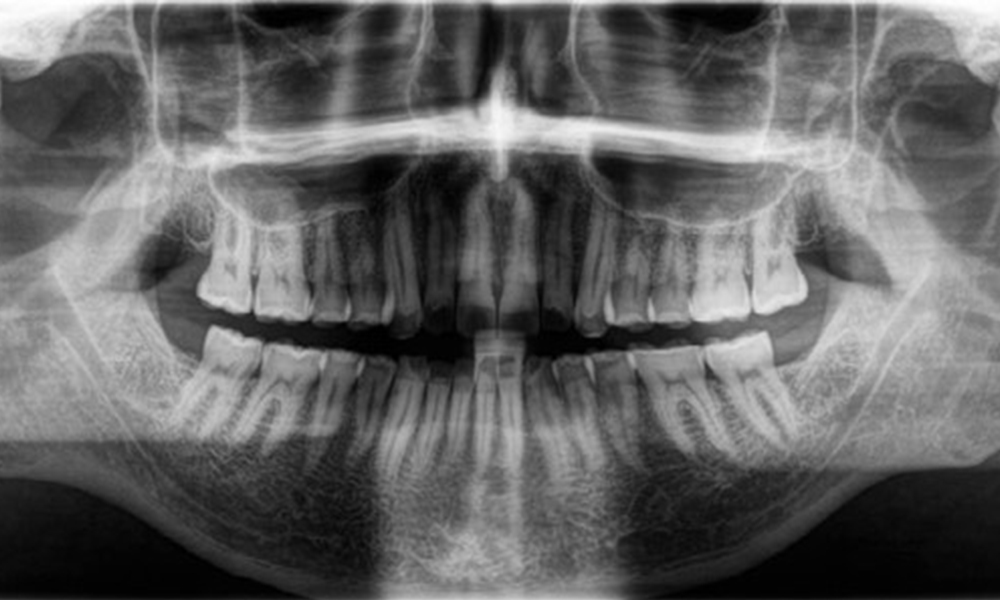

The patient has full dentition with a total of 28 teeth. There were noteworthy erosions and attritions. (Fig. 4, Fig. 5). Due to bruxism, the patient has been wearing a splint with an adjusted bite block at night for many years. The erosions were caused by long-term consumption of isotonic beverages. No periodontal bone loss or active caries were observed.

Radiological findings

Full complement of adult teeth with no caries or radiologically recognizable bone loss was observed (Fig. 6). Radiological enamel and cusp loss were particularly evident on 36 and 37.